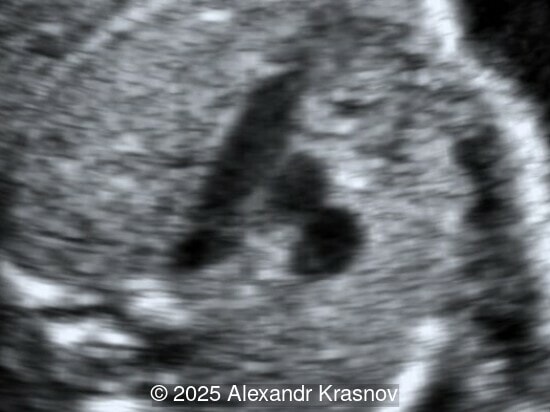

Image 2

Our ultrasound showed biometry data corresponding to 21 weeks of gestation. During echocardiography, an abnormal drainage of the pulmonary veins was detected in which the pulmonary veins drain into a venous collector linked to the superior vena cava. The four-chamber view and the three-vessel view were altered and raised suspicion of a pathology. The grayscale and color Doppler images of the four-chamber view indicate a smooth posterior wall of the left atrium, increased distance between the left atrium and the descending aorta and the absence of pulmonary veins entering the left atrium (Image 1, 2; Video 1, 2). In the three-vessel view, the diameter of the superior vena cava appears larger than that of the aorta (Image 3, Video 3). In the images of the venae cava, a significant difference is seen between the diameters of the inferior and superior vena cava with significant enlargement of the superior vena cava (Image 4, Video 4). Additionally, there is a pulmonary venous confluent chamber (“twig sign”) behind the left atrium (Image and Video 5). A vertical ascending vein connects the confluent chamber with the superior vena cava where it drains blood from the pulmonary veins (Images 6, 7; Video 6).